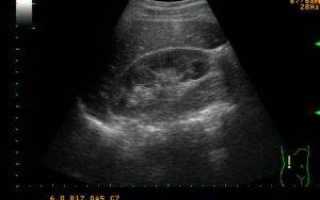

image

При подозрении на пиелонефрит проводятся лабораторные и инструментальные исследования (рентгенологическое, ультразвуковое и другие), направленные на поиск очага воспаления, определение степени поражения почек.